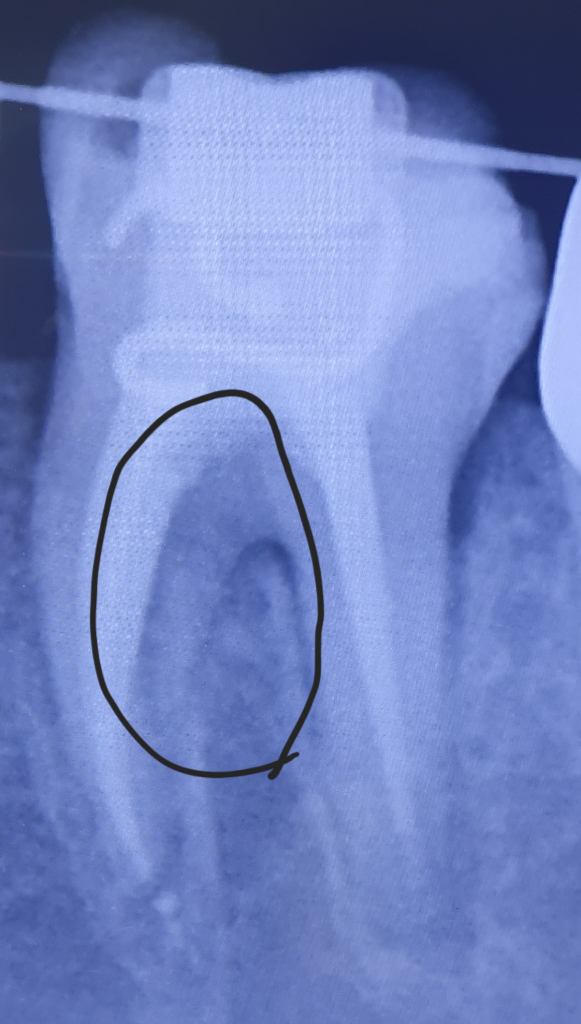

작년에 2번째어금니쪽 신경치료를 다 했는데

너무아픈데 원인이 뭔가요?

제가 동그라미 표시한 부분이 다른부분에 비해

쫌더 검은색으로 보이는데

사진이 원래 어두워서 그렇게 보이는건 가요??

잇몸에 염증이 생겨서 그럴수도 잇으며 저 까만부위는 치아의 인대가 늘어나서 보이는 거 같습니다. 일단 잇몸치료를 먼저 받아보세요.

해단부위는 치아의 뿌리가 이개 되는 부분으로 어둡게 보닝수 잌ㅅ습니다

치아에 너무과도한힘이가해지는 경우 치주인대에 자극이 되어 방사선에 어두울수 있습니다 치아에 가해지는 힘을 줄이시고 그래도 통증이 있다면 재신경치료가 필요할수 있습니다

신경 치료를 한 부위에 통증이 있는 경우 신경이 완전히 다 제거되지 않아 나타나게 됩니다. 이 경우 다시 치과에 내원하여 상태를 확인하고 추가적인 치료가 필요로 됩니다.